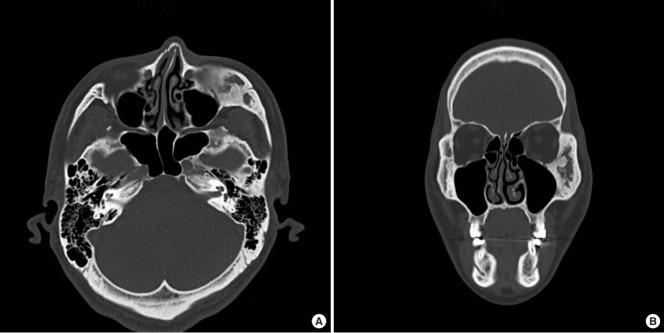

Fibrous dysplasia (FD) is a rare, benign bone disease with abnormal bone maturation and fibroblastic proliferation. Optimal treatment of zone 1 craniofacial FD is radical resection and reconstruction. To achieve of structural, aesthetic, and functional goals, we use three-dimensionally designed calvarial bone graft for reconstruction of zygomatic defect after radical resection of FD. The authors used a rapid-prototyping model for simulation surgery for radical resection and immediate reconstruction. Donor site was selected from parietal bone reflect shape, contour, and size of defect. Then radical resection of lesion and immediate reconstruction was performed as planned. Outcomes were assessed using clinical photographs and computed tomography scans. Successful reconstruction after radical resection was achieved by three-dimensional calvarial bone graft without complications. After a 12-month follow-up, sufficient bone thickness and symmetric soft tissue contour was well-maintained. By considering three-dimensional configuration of zygomaticomaxillary complex, the authors achieved satisfactory structural, aesthetic and functional outcomes without complications.

骨纤维异常增殖症(FD)是一种罕见的良性骨病,伴有异常的骨成熟和成纤维细胞增殖。颅面部1区FD的最佳治疗方法是根治性切除和重建。为了实现结构、美学和功能目标,我们使用三维设计的颅骨移植来重建FD根治性切除后的颧骨缺损。作者使用快速成型模型进行根治性切除和即刻重建的模拟手术。供骨部位选自顶骨,以反映缺损的形状、轮廓和大小。然后按计划进行病变的根治性切除和即刻重建。使用临床照片和计算机断层扫描评估结果。通过三维颅骨移植成功实现了根治性切除后的重建,且无并发症。经过12个月的随访,充分的骨厚度和对称的软组织轮廓得到了良好维持。通过考虑颧骨上颌复合体的三维结构,作者获得了满意的结构、美学和功能效果,且无并发症。